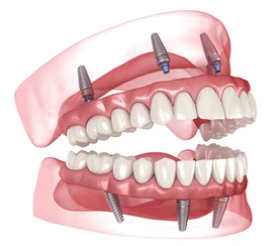

Solution souvent préconisée par les chirurgiens-dentistes, notamment pour les patients ne disposant pas d’une masse osseuse importante : la pose d’une prothèse fixée sur 4 ou 6 implants dentaires dans l’os maxillaire, avec une dentition artificielle ancrée sur un arc prothétique dentaire complet en céramique ou résine. Ces prothèses dentaires fixes soutenant 10 à 14 dents artificielles par mâchoire, sont appelées “All On” et déclinées en All-On 4, All-On 6, selon le nombre d’implants dentaires associés. Le système offre une solution bien plus durable, plus confortable et plus facile à entretenir que les dentiers classiques, ainsi qu’un confort de mastication et un rendu esthétique naturel optimaux. Selon son diagnostic le chirurgien-dentiste préconisera le traitement All-On le mieux adapté.

Solution souvent préconisée par les chirurgiens-dentistes, notamment pour les patients ne disposant pas d’une masse osseuse importante : la pose d’une prothèse fixée sur 4 ou 6 implants dentaires dans l’os maxillaire, avec une dentition artificielle ancrée sur un arc prothétique dentaire complet en céramique ou résine. Ces prothèses dentaires fixes soutenant 10 à 14 dents artificielles par mâchoire, sont appelées “All On” et déclinées en All-On 4, All-On 6, selon le nombre d’implants dentaires associés. Le système offre une solution bien plus durable, plus confortable et plus facile à entretenir que les dentiers classiques, ainsi qu’un confort de mastication et un rendu esthétique naturel optimaux. Selon son diagnostic le chirurgien-dentiste préconisera le traitement All-On le mieux adapté.

Le traitement All-On 4 est une prothèse dentaire permanente venant remplacer toutes les dents, en haut ou/et en bas de la mâchoire. Elle est constituée d’un bridge porté sur un arc prothétique complet qui vient se fixer sur 4/6 implants chirurgicalement implantés dans l’os maxillaire du patient. En haut, deux implants sont ainsi placés dans la partie avant de l’os maxillaire, et deux ou quatre autres sont implantés au fond avec un angle évitant les cavités du sinus. Pour une pose sur la mâchoire inférieure (mandibule), les deux implants postérieurs vont être placés dans un angle évitant le nerf inférieur. L’arc prothétique, constitué de fausses gencive en résine et de dents en céramique, porcelaine ou résine vient compléter le dispositif.

Le traitement All-On 4 est une prothèse dentaire permanente venant remplacer toutes les dents, en haut ou/et en bas de la mâchoire. Elle est constituée d’un bridge porté sur un arc prothétique complet qui vient se fixer sur 4/6 implants chirurgicalement implantés dans l’os maxillaire du patient. En haut, deux implants sont ainsi placés dans la partie avant de l’os maxillaire, et deux ou quatre autres sont implantés au fond avec un angle évitant les cavités du sinus. Pour une pose sur la mâchoire inférieure (mandibule), les deux implants postérieurs vont être placés dans un angle évitant le nerf inférieur. L’arc prothétique, constitué de fausses gencive en résine et de dents en céramique, porcelaine ou résine vient compléter le dispositif.